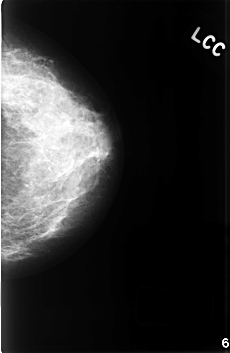

C_0393_1.LEFT_CC

LEFT_CC LINES 4584 PIXELS_PER_LINE 2984 BITS_PER_PIXEL 12 RESOLUTION 50 NON_OVERLAY